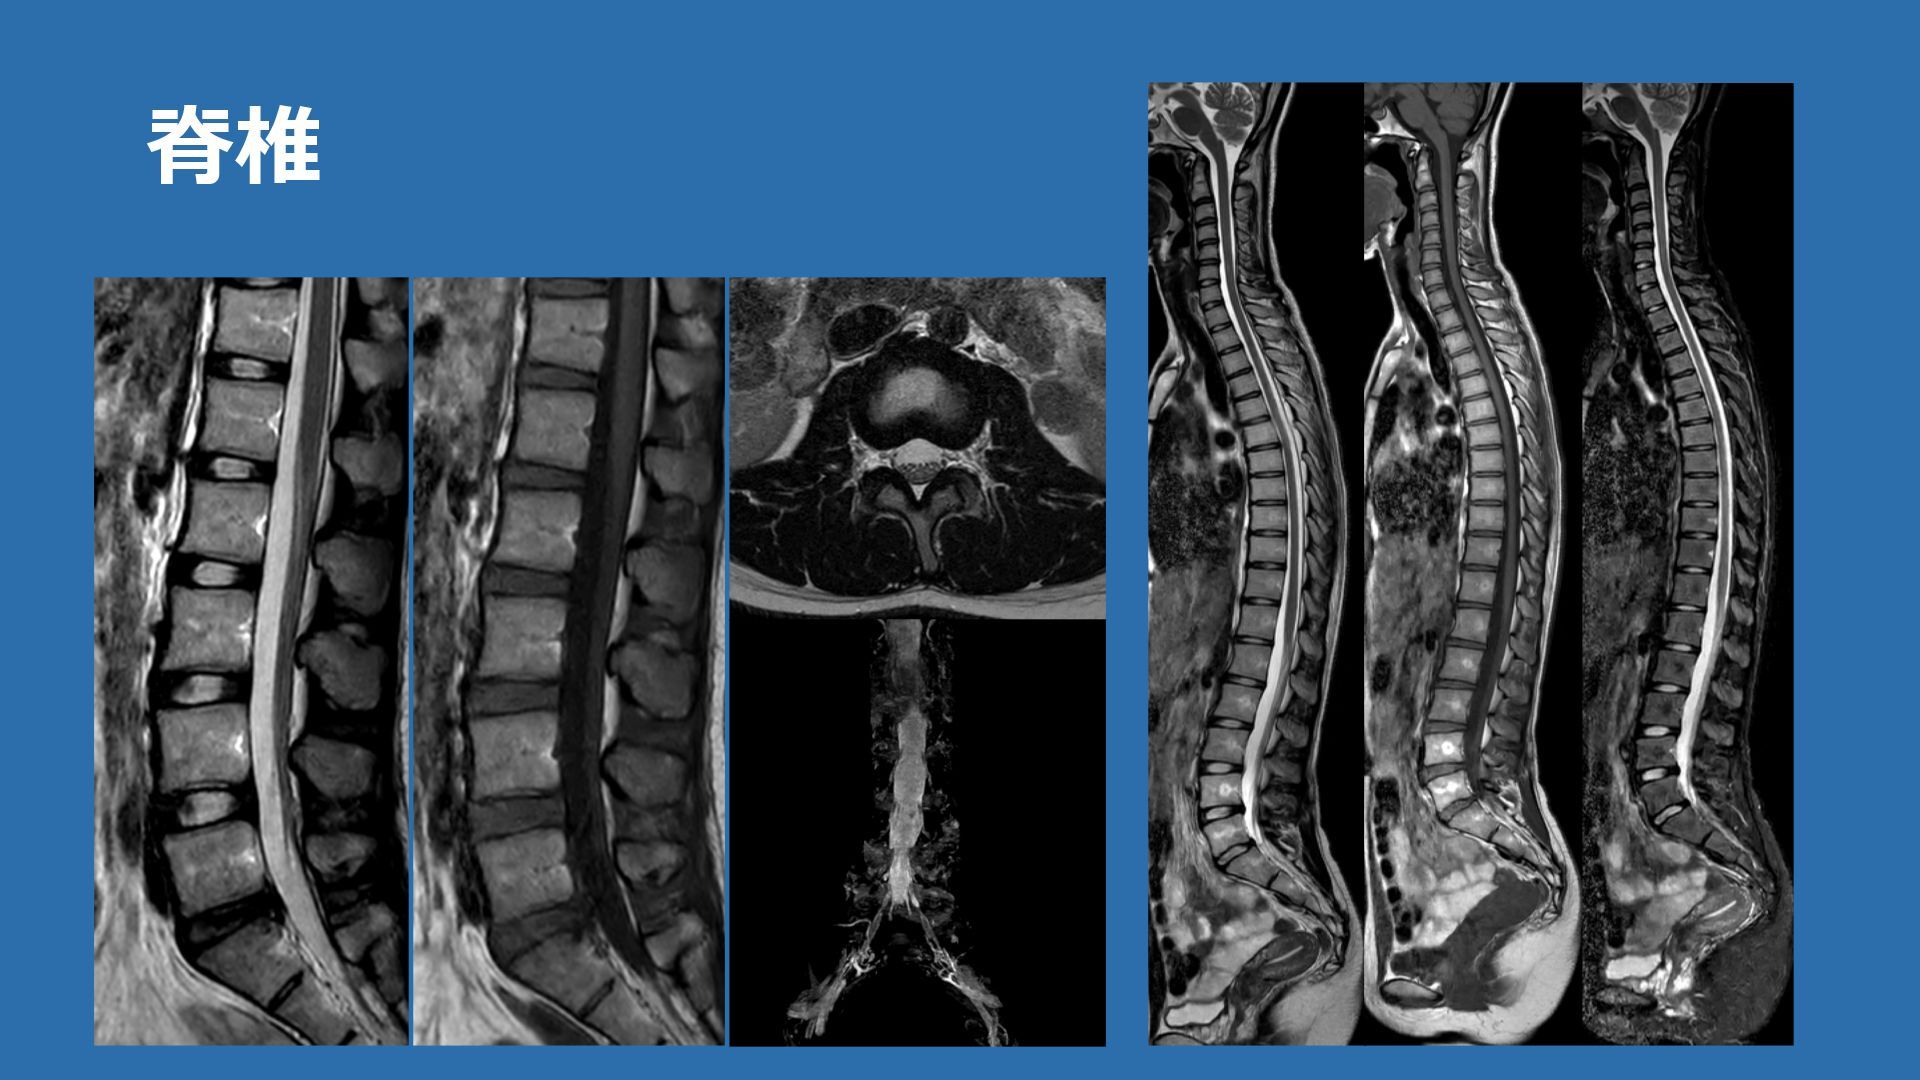

脊椎